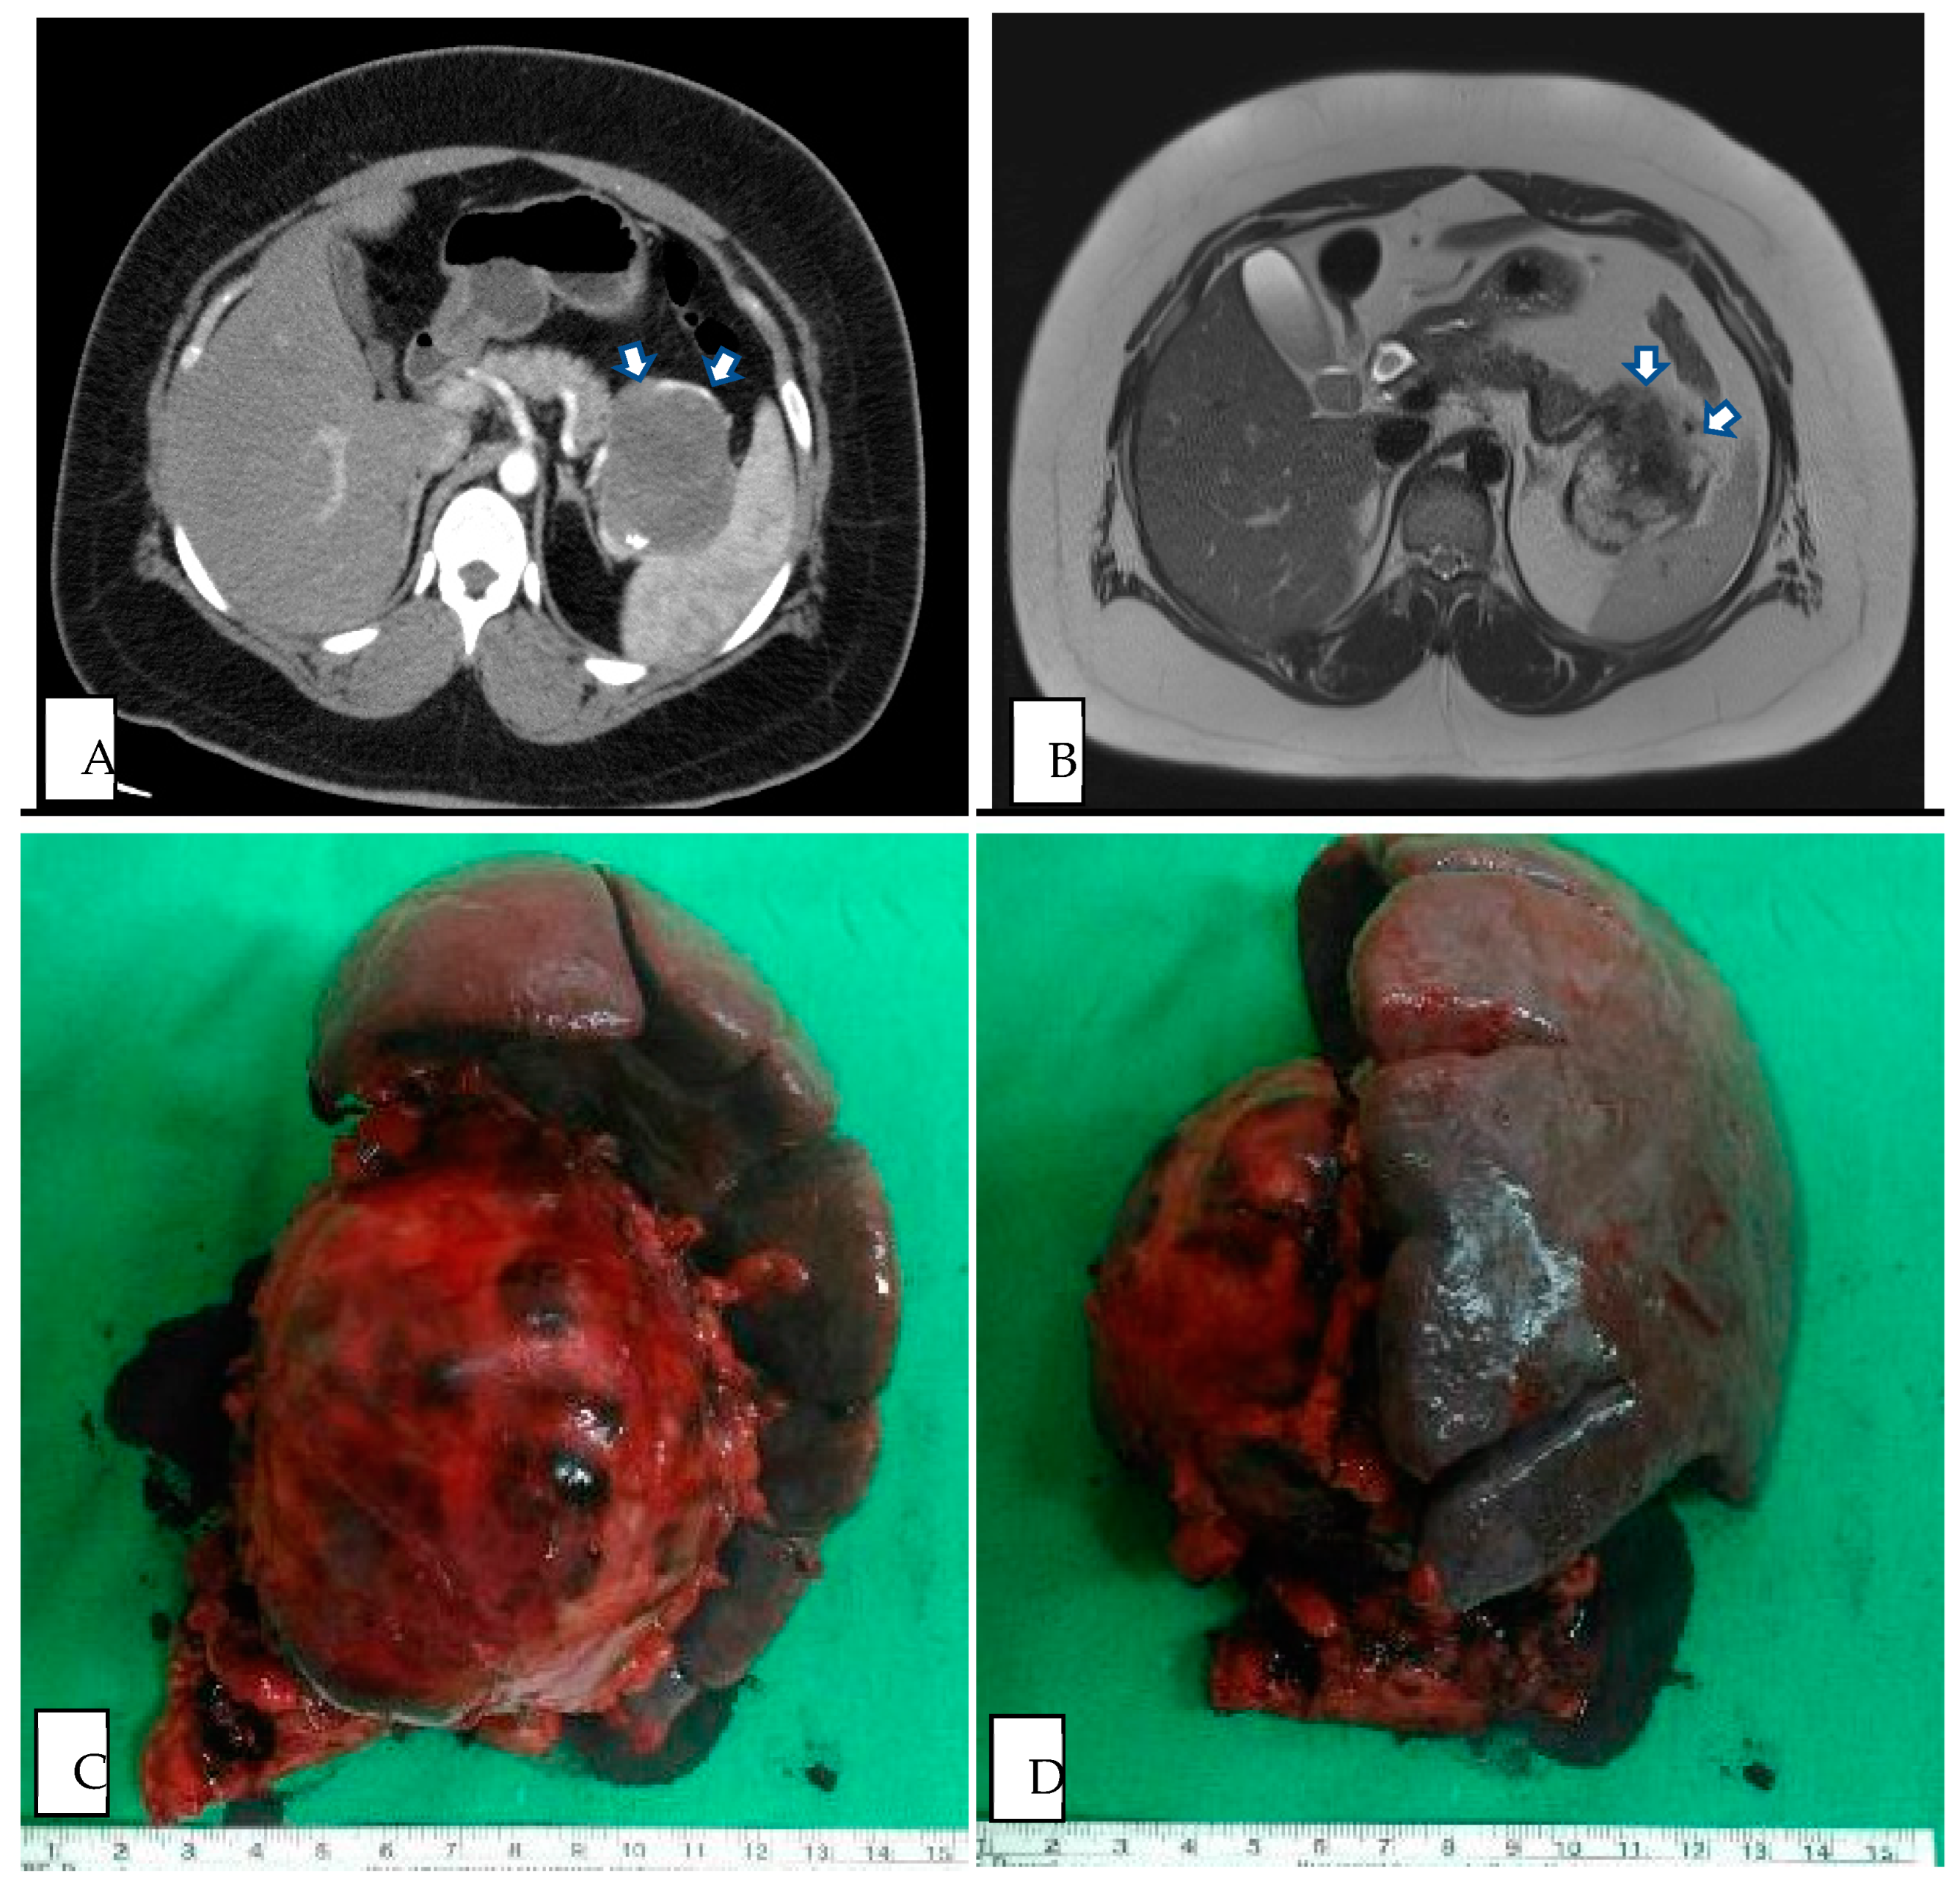

Figure 3.

(A) Preoperative CT image of SPN in pancreatic tail (axial plane, venous phase). (B) Preoperative MRI image of SPN in pancreatic tail (axial plane, T2 weighted). (C) Intraoperative specimen of DP with splenectomy from SPN in pancreatic tail, ventral view. (D) Intraoperative specimen of DP with splenectomy from SPN in pancreatic tail, dorsal view. White arrow demarcates region of pancreatic tail mass.

All of our patients had preoperative radiologic findings in either US, CT, or MRI. Most showed typical features of SPN (Figure 2 and Figure 3), such as oval, exophytic, and regular capsulated lesions with a mixed cystic and solid component but were almost entirely solid or cystic with thick walls [7]. Preoperative imaging studies included US (10/24 cases), CT (23/24 cases), and MRI (14/24 cases). In total, nine cases were diagnosed as SPNs based on preoperative imaging, four cases based on CT (17%), and five cases based on MRI (36%) (Table 1). The CT modalities are shown in Table 2; all tumor margins were clear in preoperative images. No hemorrhage, parenchyma atrophy, or invasion of adjacent vessels and abdominal organs was seen. More irregular shaping was seen in SPNs of the pancreatic head (p = 0.037). The cystic component was significantly more prominent in the SPN of the pancreatic tail (p = 0.035). Pancreas or bile duct dilation was mostly seen in the pancreatic head in our patient (p < 0.001).